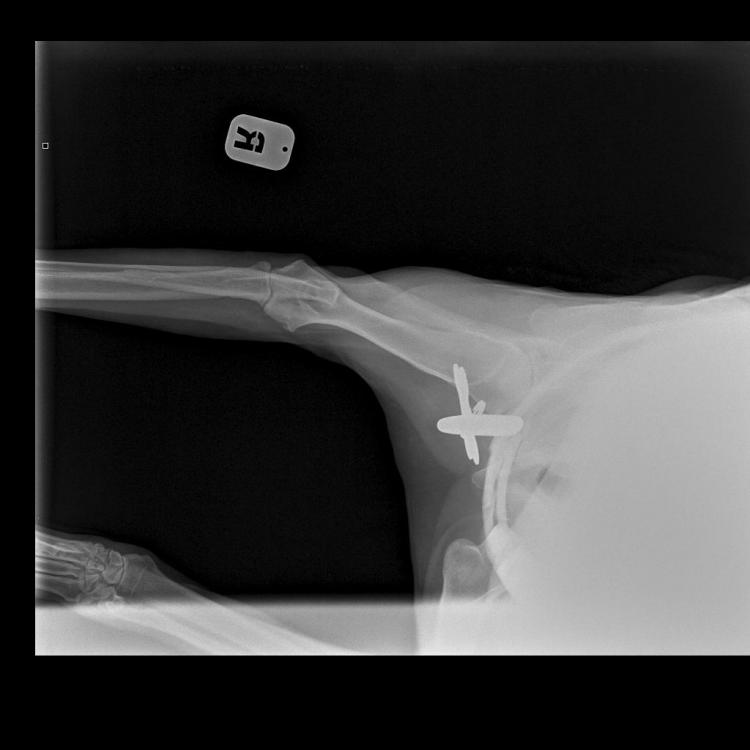

Яся&Лина&Лора Опубликовано 4 июня, 2020 Опубликовано 4 июня, 2020 Теперь все по порядку. Друзья, спасибо за терпение и выдержку! Писала на бегу. И, конечно же, спасибо за поддержку! В общем, Никуня нас немножко сегодня испугала, если честно. Поэтому побежали не раздумывая, выяснять что случилось с лапой. Как понимаете, боишься уже всего! В клинике нас встретил давно знакомый и совсем не страшный доктор Климухин И.Н. Очень внимательно и долго нас осматривал и щупал. Потом уже в конце приема сказал, что Никуся невероятно терпеливая девочка, молчит и терпит до последнего, даже никаких звуков не издаёт. Потом мы сделали 3 рентгеновских снимка и сдали кровь: общий и б/х (для контроля перед назначением обезболивающих). Кровь сдавали и температуру мерили с настоящим голдячим достоинством! Ну, правда... немножко случилась экспресс-линька.... Мне кажется, в Нике осталась вся клиника! Доктор нам отзвонился по анализам очень быстро. Анализы у нас прекрасные! Ура! За исключением повышенных лейкоцитов. Поэтому нужен контроль на фоне лечения через несколько дней. По рентгену криминала тоже нет никакого. По результату осмотра, есть небольшие проблемки с суставами, но ничего критичного. При этом, однозначно есть хромота на правую лапку, а реагирует при осмотре и левая тоже. Предположили, что, возможно, Никуся неудачно кувырнулась дома или оступилась?! Последнее время дожди и мы никуда не выезжали. Дома Никуся на диван залазит крайне редко. Внизу травмироваться вроде как негде?! Гуляет она всегда с огромным удовольствием. Возможно, на улице неудачно рванула вперед. Но, слава Богу! Ничего не порвала! И не вывихнула! В итоге доктор нам назначил Превикокс на 5 дней. В воскресенье ждет нас на контрольный осмотр, чтоб оценить динамику и надо будет повторить общий анализ крови, посмотреть лейкоциты. Счастью не было предела, волшебное слово «домой»! За все страдания получила немного вкуснях. «Где тут вкусняхи дают?» «Ням ням» «А мы уже домой?! Правда?!» «Тогда можно и расслабится!» «Поехали уже! Че стоим?!» 7